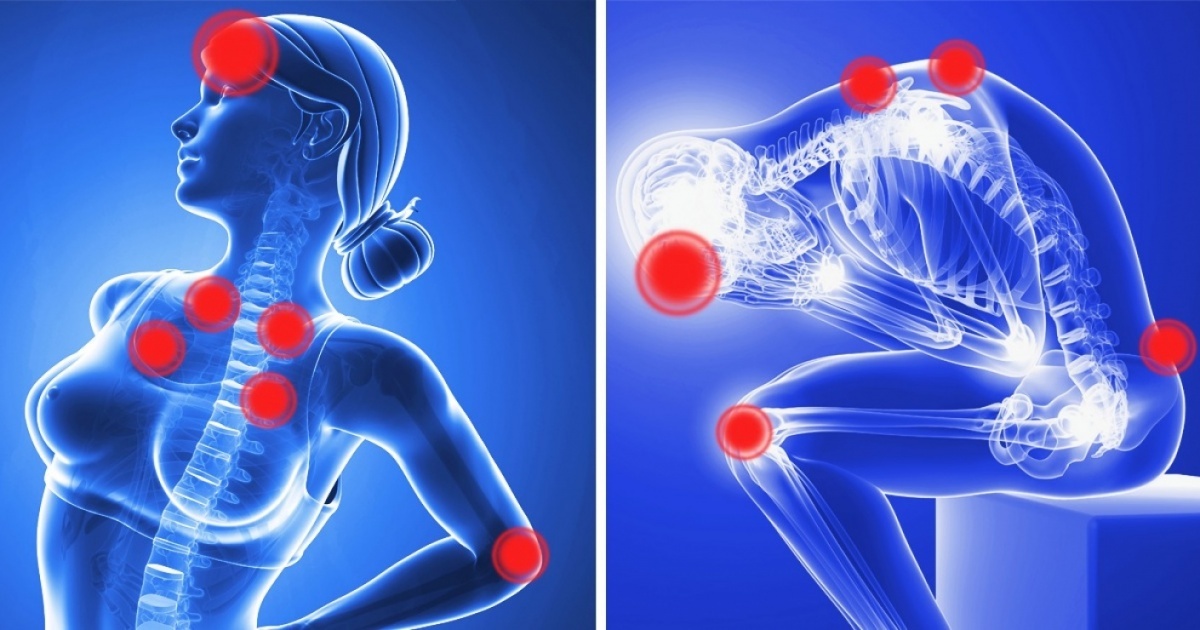

Изображения и визуализация внутренних органов человека

Раздел: Секреты мастерства